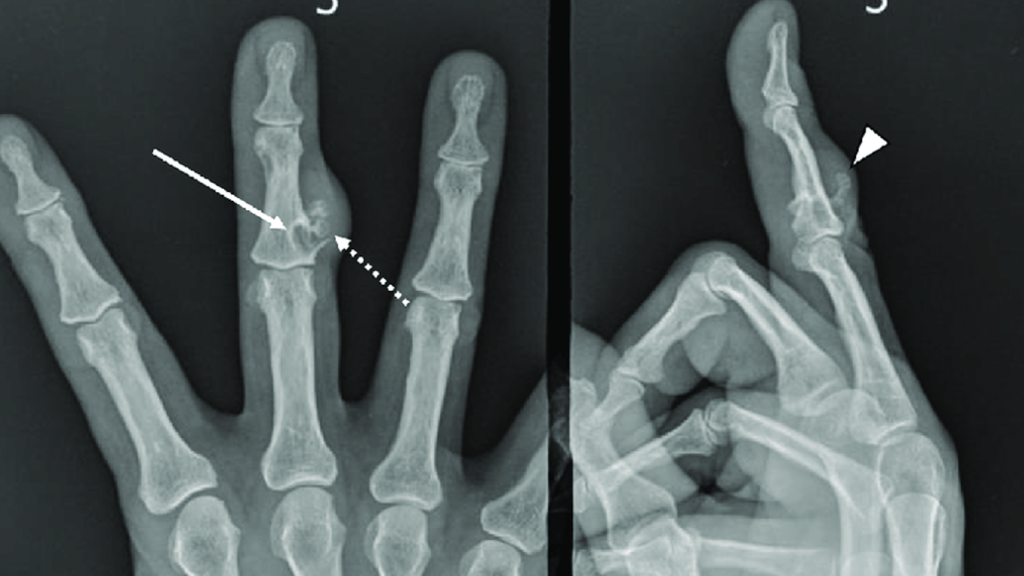

روش های تشخیص در رفتگی انگشت دست چیست؟

برای تشخیص دادن اینکه آیا انگشت دست شما در رفته است یا خیر پزشک از روشهای مختلفی استفاده میکند که در ادامه هر کدام از آنها را به شما معرفی میکنیم.

انجام دادن معاینه بالینی توسط پزشک